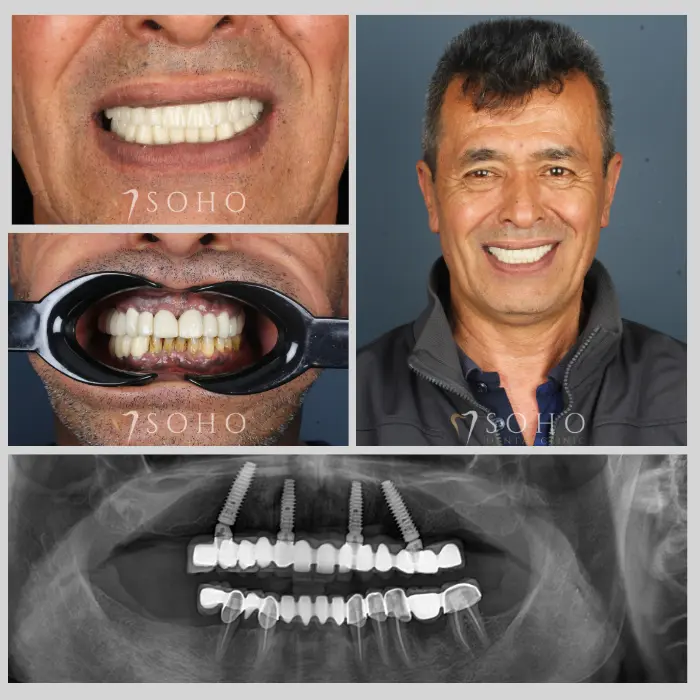

Real Patients. Real Smiles.

Explore the journey of our international patients through authentic visuals, elegant transformations, and moments captured inside Soho Dental Clinic. Let their stories inspire your own.

From First Visit to Final Smile.

Explore real patient stories captured in every transformation. These are more than smiles — they are renewed confidence, achieved with care and precision at Soho Dental Clinic.